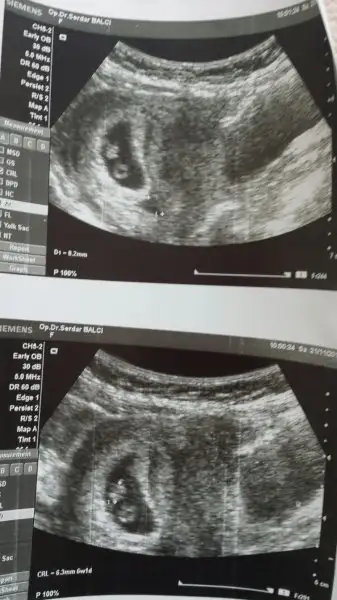

Plesenta sağda kız ama kesenin içindeki bebeğin konumunu pek anlayamadımbu usg de yorumlayabilir misiniz?

canım ilginc olanı bu usg aldıktan sonra ertesi gün başka bir doktora gittim ve kese çok farklıydı bak gönderiyorum. bir gün aralıkla farklı usg resimleri bir kız bir erkek mi olacak yaniPlesenta sağda kız ama kesenin içindeki bebeğin konumunu pek anlayamadım

Aaa evet burada erkek gibi plesentanın konumu Bebek erkek gibi burada ama ortada hiç belli olmazcanım ilginc olanı bu usg aldıktan sonra ertesi gün başka bir doktora gittim ve kese çok farklıydı bak gönderiyorum. bir gün aralıkla farklı usg resimleri bir kız bir erkek mi olacak yani

benimde kafam senin ki gibi karışık...yani ekranda gördügün gibi cıkmadı usg de dimi yani benim tek inandıgım doktor karnının hangi tarafından baktı? benim solumdan baktı ama usg resimi karnıma tutunca sagımda kalıyor:-/ keşke sana yardımcı olabilsem ama bende anlamıyorumkivilcim82 canım ben geçen hafta yani 6 hafta bitiminde ultrasona girdim karşımdaki ekranda bebeği sağa yapışık gördümm fakat doktor bana usg kağıdını verirken o noktayı büyütüp vermiş bu nedenle kağıtta hiç belli değil... Ben de heyecanlanıyodum alıcam burada paylaşıcam diye ama anlaşılır değil yani...